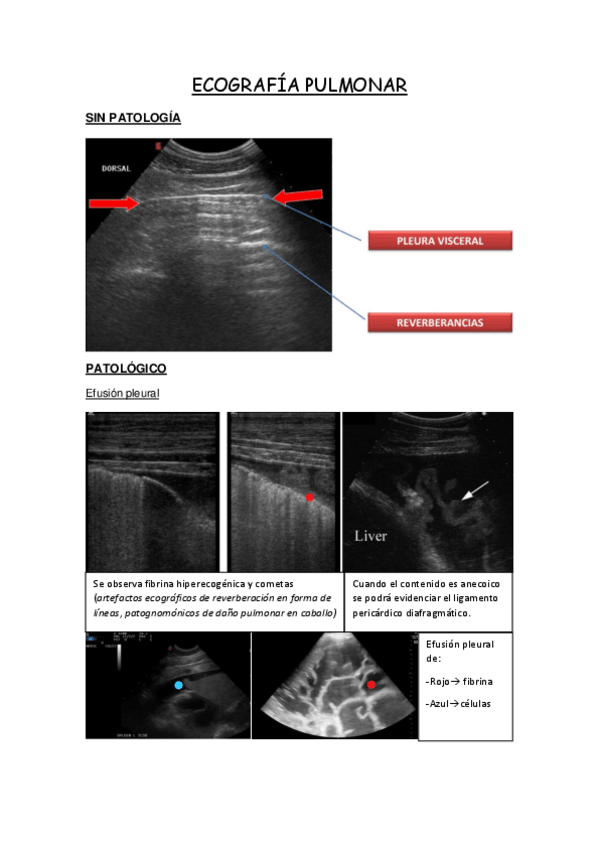

IMÁGENES RADIOLÓGICAS ÉQUIDOS

He publicado nuevos apuntes de 3º Diagnóstico Por Imagen: IMÁGENES RADIOLÓGICAS ÉQUIDOS

ECOGRAFIA-PULMONAR-EQUIDOS.pdf